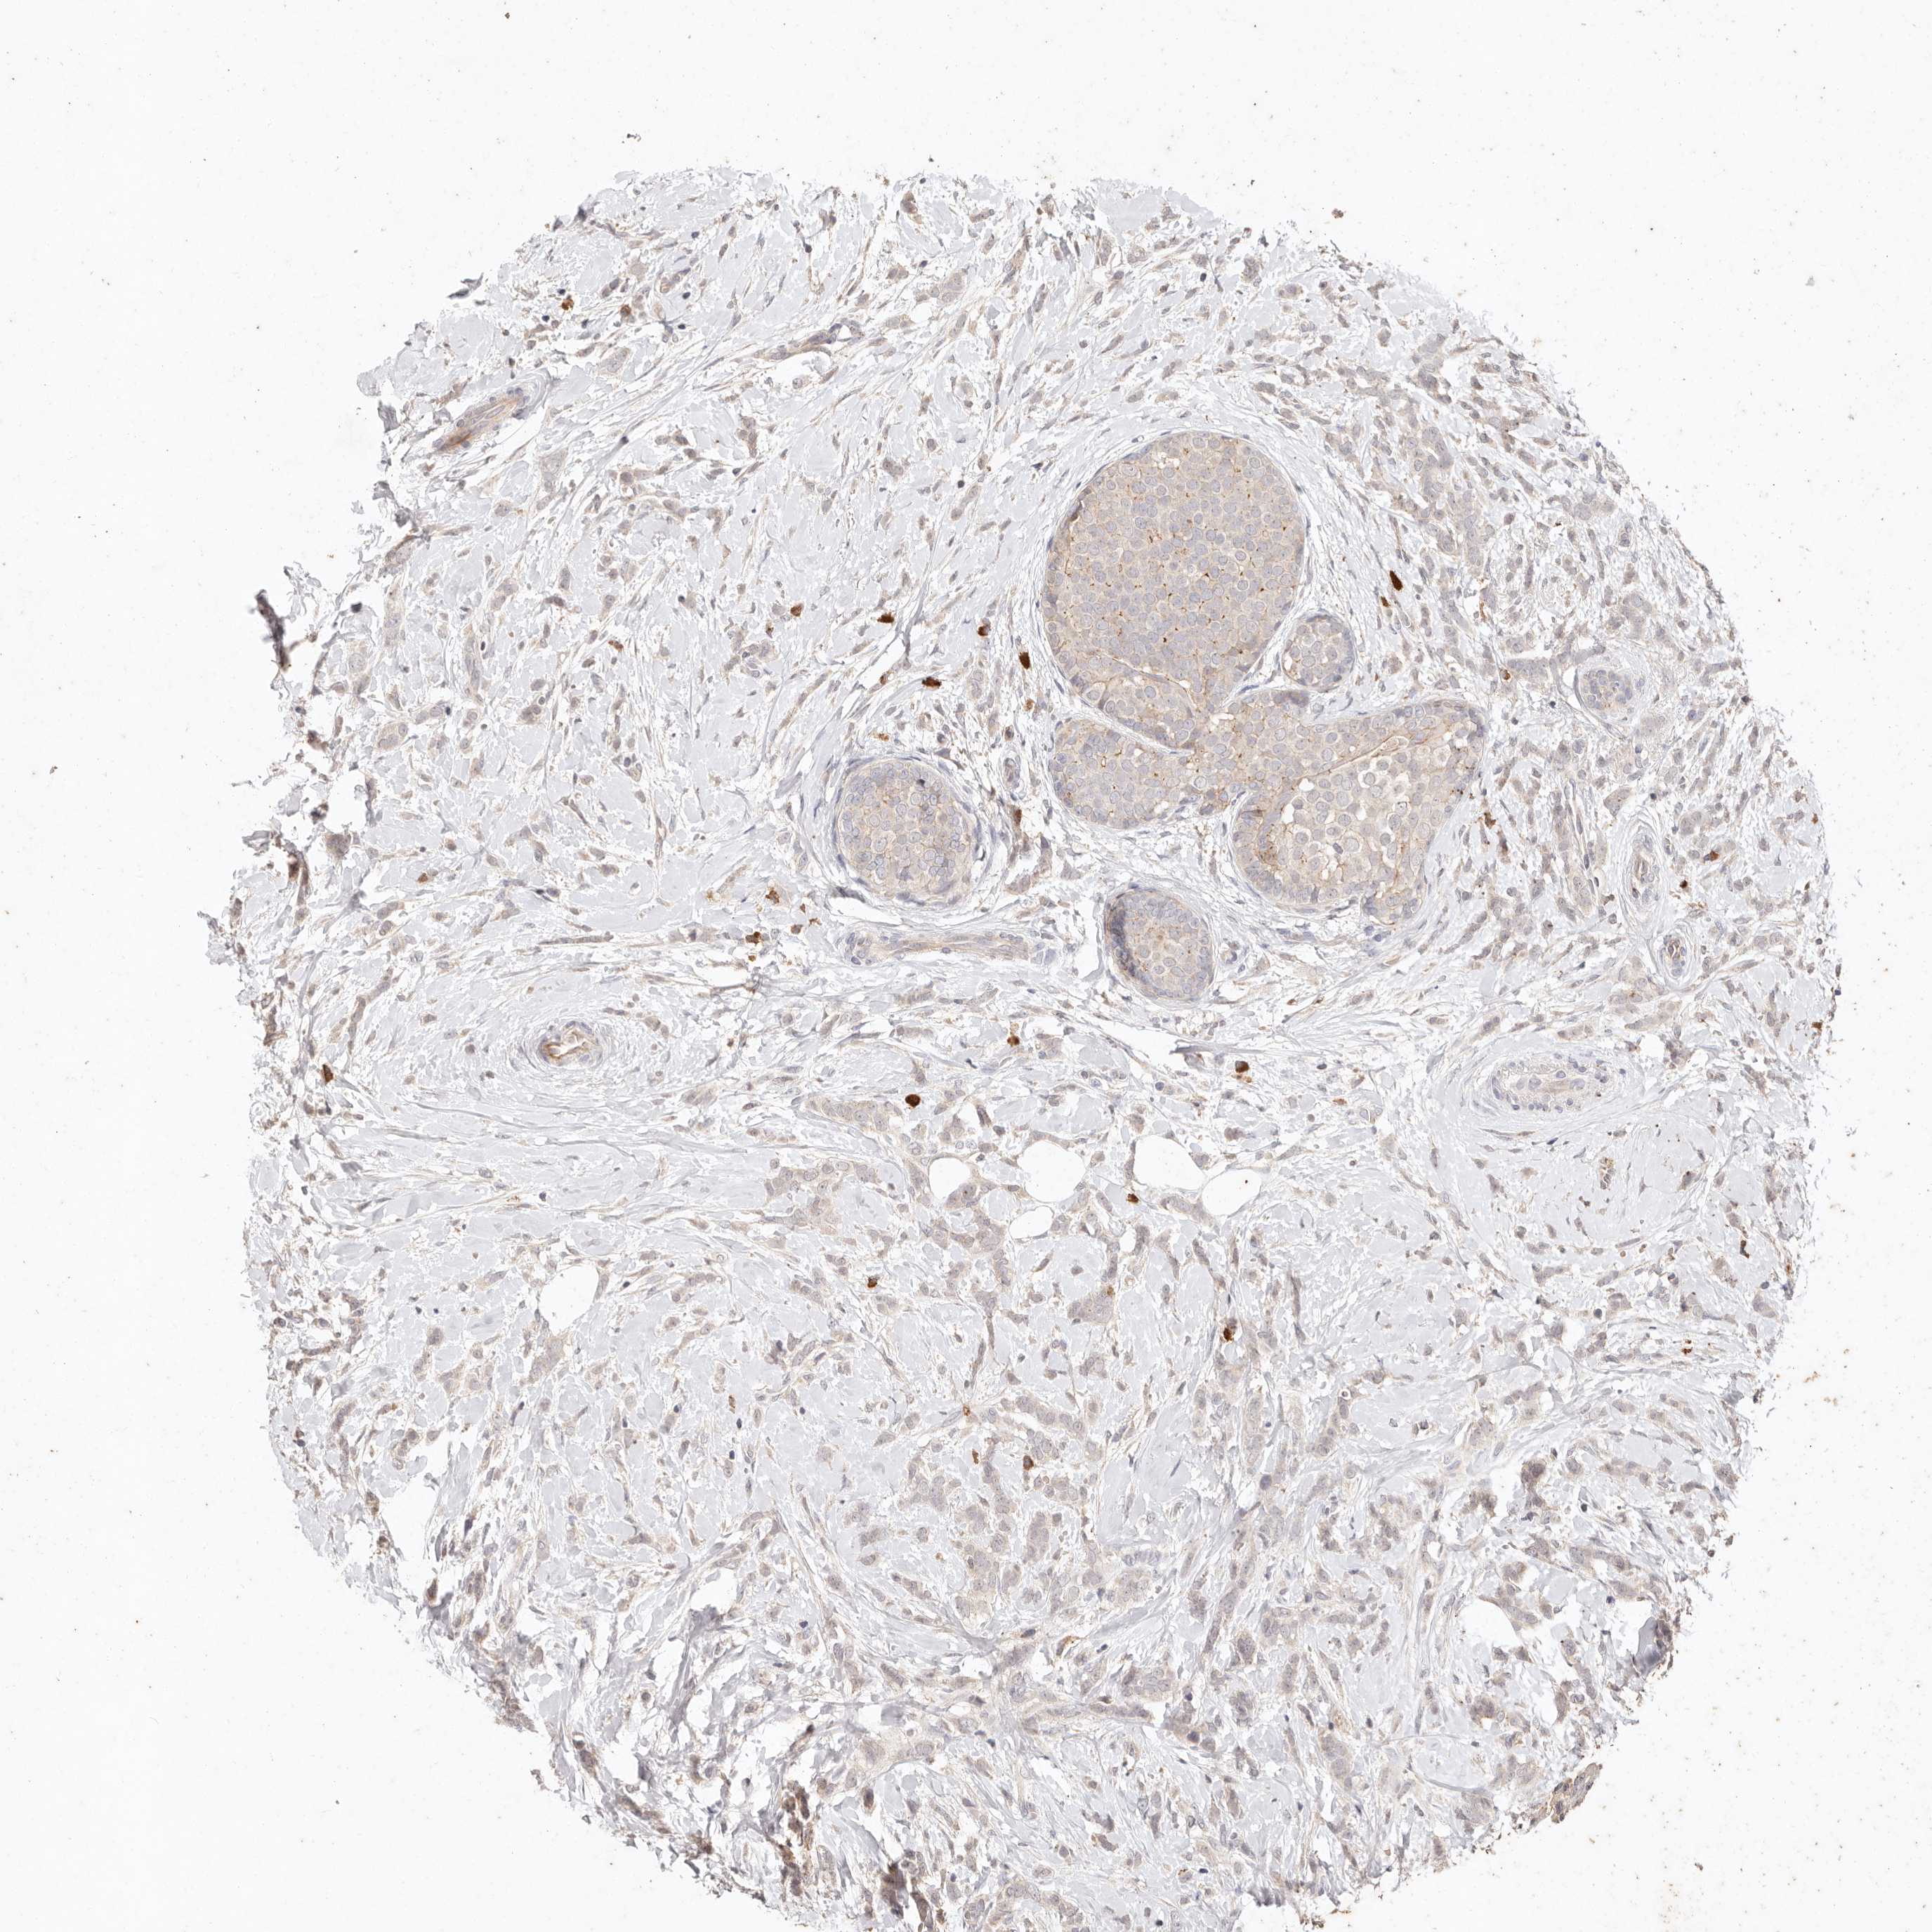

CANCER BREAST CANCER Show tissue menu

BRCA TCGA BRCA VALIDATION PROTEIN EXPRESSION

ANTIBODIES

AND

VALIDATION